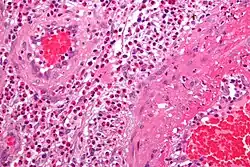

Pathologie

Feingeweblich zeigt sich eine starke Vermehrung eosinophiler Granulozyten im Gewebe (Gewebseosinophilie), mit Befall vor allem der kleinen Blutgefäße (mit Zerstörung, Blutgerinnselbildung und daraus resultierenden Infarkten). Daneben kann die Entzündung auch direkt auf verschiedene Organe übergreifen, z. B. auf das Herz mit der Folge einer eosinophilen Herzmuskelentzündung.